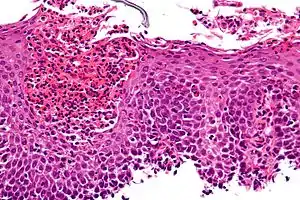

The esophagus is a muscular tube made of both voluntary and involuntary muscles. It is responsible for peristalsis of food. It is about 8 inches long and passes through the diaphragm before entering the stomach. The esophagus is made up of three layers: from the inside out, they are the mucosa, submucosa, muscularis externa. The mucosa, the inner most layer and lining of the esophagus, is composed of stratified squamous epithelium, lamina propria, and muscularis mucosae. At the end of the esophagus is the lower esophageal sphincter, which normally prevents stomach acid from entering the esophagus.

If the sphincter is not sufficiently tight, it may allow acid to enter the esophagus, causing inflammation of one or more layers. Esophagitis may also occur if an infection is present, which may be due to bacteria, viruses, or fungi; or by diseases that affect the immune system.[5]

Irritation can be caused by GERD, vomiting, surgery, medications, hernias, and radiation injury.[5] Inflammation can cause the esophagus to narrow, which makes swallowing food difficult and may result in food bolus impaction.